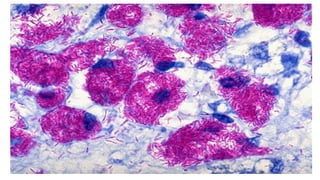

• Coloração de Ziehl-Neelsen/ Coloração álcool-ácido resistente

• Utilizada para identificar todas as bactérias do gênero Mycobacterium

• Mycobacterium tuberculosis, o agente causador da tuberculose, e

• Mycobacterium leprae, o agente causador da lepra.

• Gênero Nocardia sp.

• Micobactérias:

• Bacilos finos

• Possuem grande quantidade ácidos

graxos (chamados de ácido micólico)

• Bactérias intracelulares obrigatórias.

Corante vermelho carbolfucsina

Coloração Ziehl-Neelsen